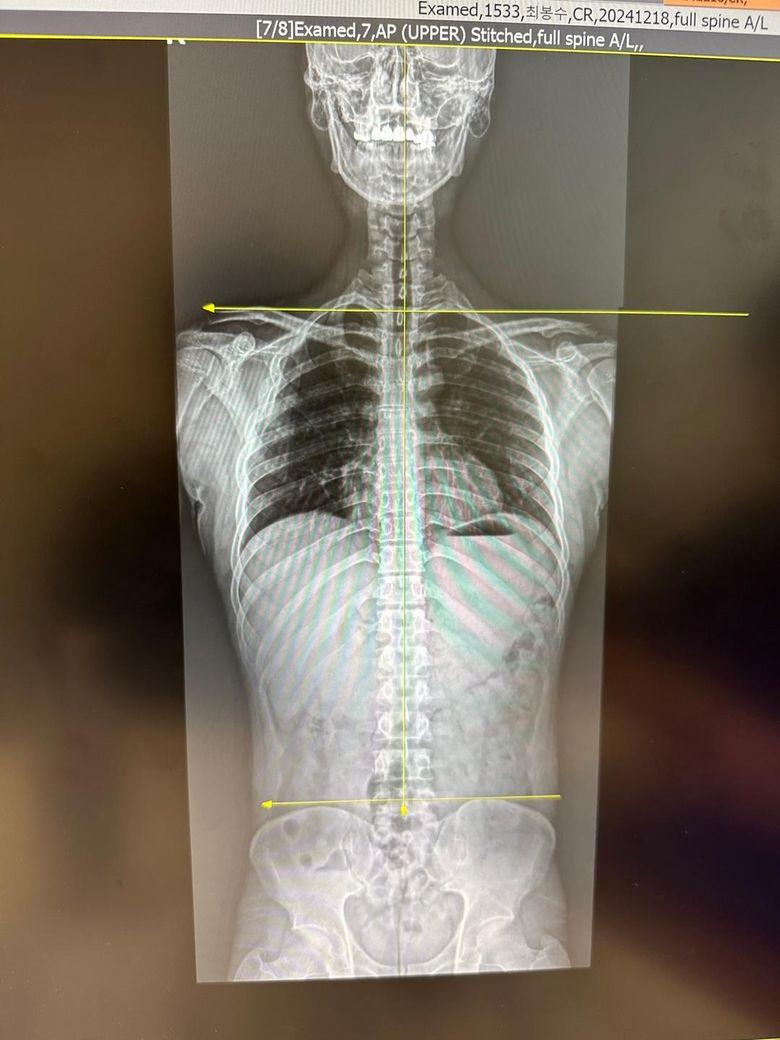

한쪽어깨 찝힘이 발생해서 엑스레이를 찍어봤습니다..

엑스레이 사진상에 보시면 제 기준 오른쪽(사진 기준 왼쪽) 어깨가 찝히는 상황이 자주 발생합니다.

그래서 엑스레이를 찍어보니 사진과 같이 양쪽 어깨 길이가 다르고, 어깨관절이 견봉쪽에 촥 달라붙어있어서 찝히는 느낌이 드는게 아닌가 합니다..

x-ray상으로 보았을 때는 골반 틀어짐이 있어서 척추, 어깨, 머리 중심도 틀어져 있습니다.